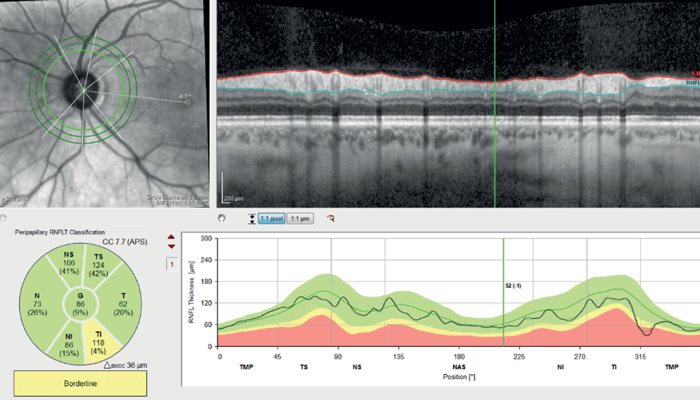

Optical Coherence Tomography Retinal Nerve Fiber Layer (OCTRNFL) with the SPECTRALIS platform (Heidelberg Engineering) revealed temporal thinning in the right eye, more in the inferotemporal quadrant (see Figure 2). Glaucoma causes retinal thinning and asymmetry in the macula (specifically in the ganglion cell layer), so we assessed OCT Macula which revealed relative asymmetry and thinning inferiorly (see Figure 3). Ganglion Cell Layer segmentation revealed generalized thinning and asymmetry between the superior and inferior hemifield.

OCT-RNFL in the left eye showed only mild thinning inferotemporally (see Figure 4) and OCT Macula showed asymmetry of retinal thickness with inferior thinning (see Figure 5).